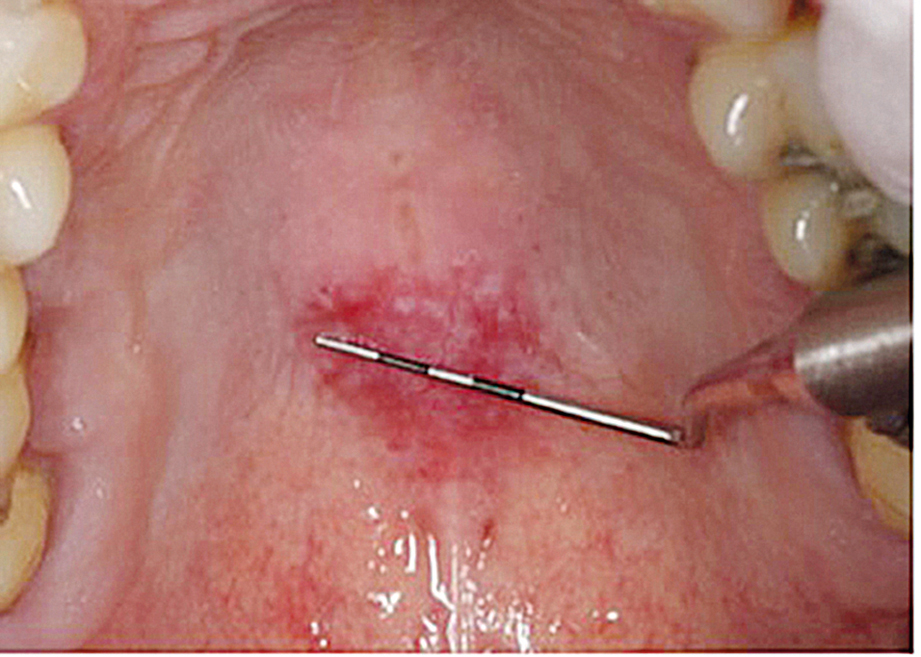

Metotrexat kan ge ulcerationer i munhålan som en koncentrationsberoende biverkning (Figur 3) [12]. Förhöjda metotrexatkoncentrationer kan i sin tur bero på en läkemedelsinteraktion med till exempel protonpumpshämmare, tetracykliner eller trimetoprim [13].

Figur 3.